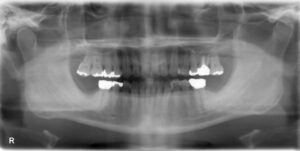

大臼歯3本欠損症例

BEFORE AFTER 74歳女性/上下3本/インプラント埋込手術 【治療内容】 欠損補綴のご相談でご来院された患者さ…